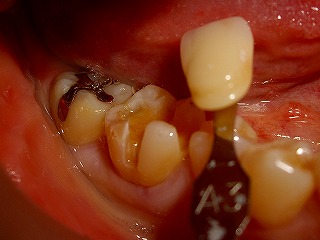

治療中右下奥歯金属インレーと金属去し

形成したところ

左上奥歯を金属からセラミッ クに変更

した

ところ